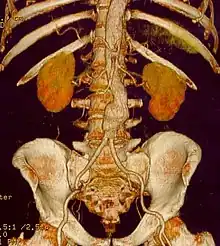

CT reconstruction image of an abdominal aortic aneurysm

A 6.5 cm AAA with a 3 cm lumen